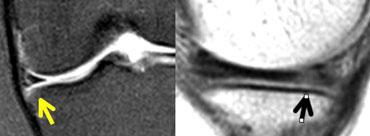

Tăng tín hiệu không chạm rõ ràng đến bề mặt. Đường đen nhỏ ở bờ dưới sụn chêm. Khi nội soi khớp, sụn chêm hoàn toàn bình thường.

Đây là một quan niệm sai lầm khi cho rằng sụn chêm phải đồng nhất giảm tín hiệu trên ảnh mật độ proton (proton-density).

Sụn chêm không nhất thiết phải có màu đen.

Chỉ khi tín hiệu cao chạm rõ ràng đến bề mặt sụn chêm, bạn mới có thể chẩn đoán rách.

Nếu còn nghi ngờ liệu tín hiệu cao có chạm đến bề mặt hay không, hãy xem xét tất cả các lát cắt lân cận.

Nếu vẫn còn nghi ngờ, không nên chẩn đoán rách.

Nếu bạn còn dấu hỏi trong đầu, hãy kết luận “sụn chêm bình thường”. (hình)